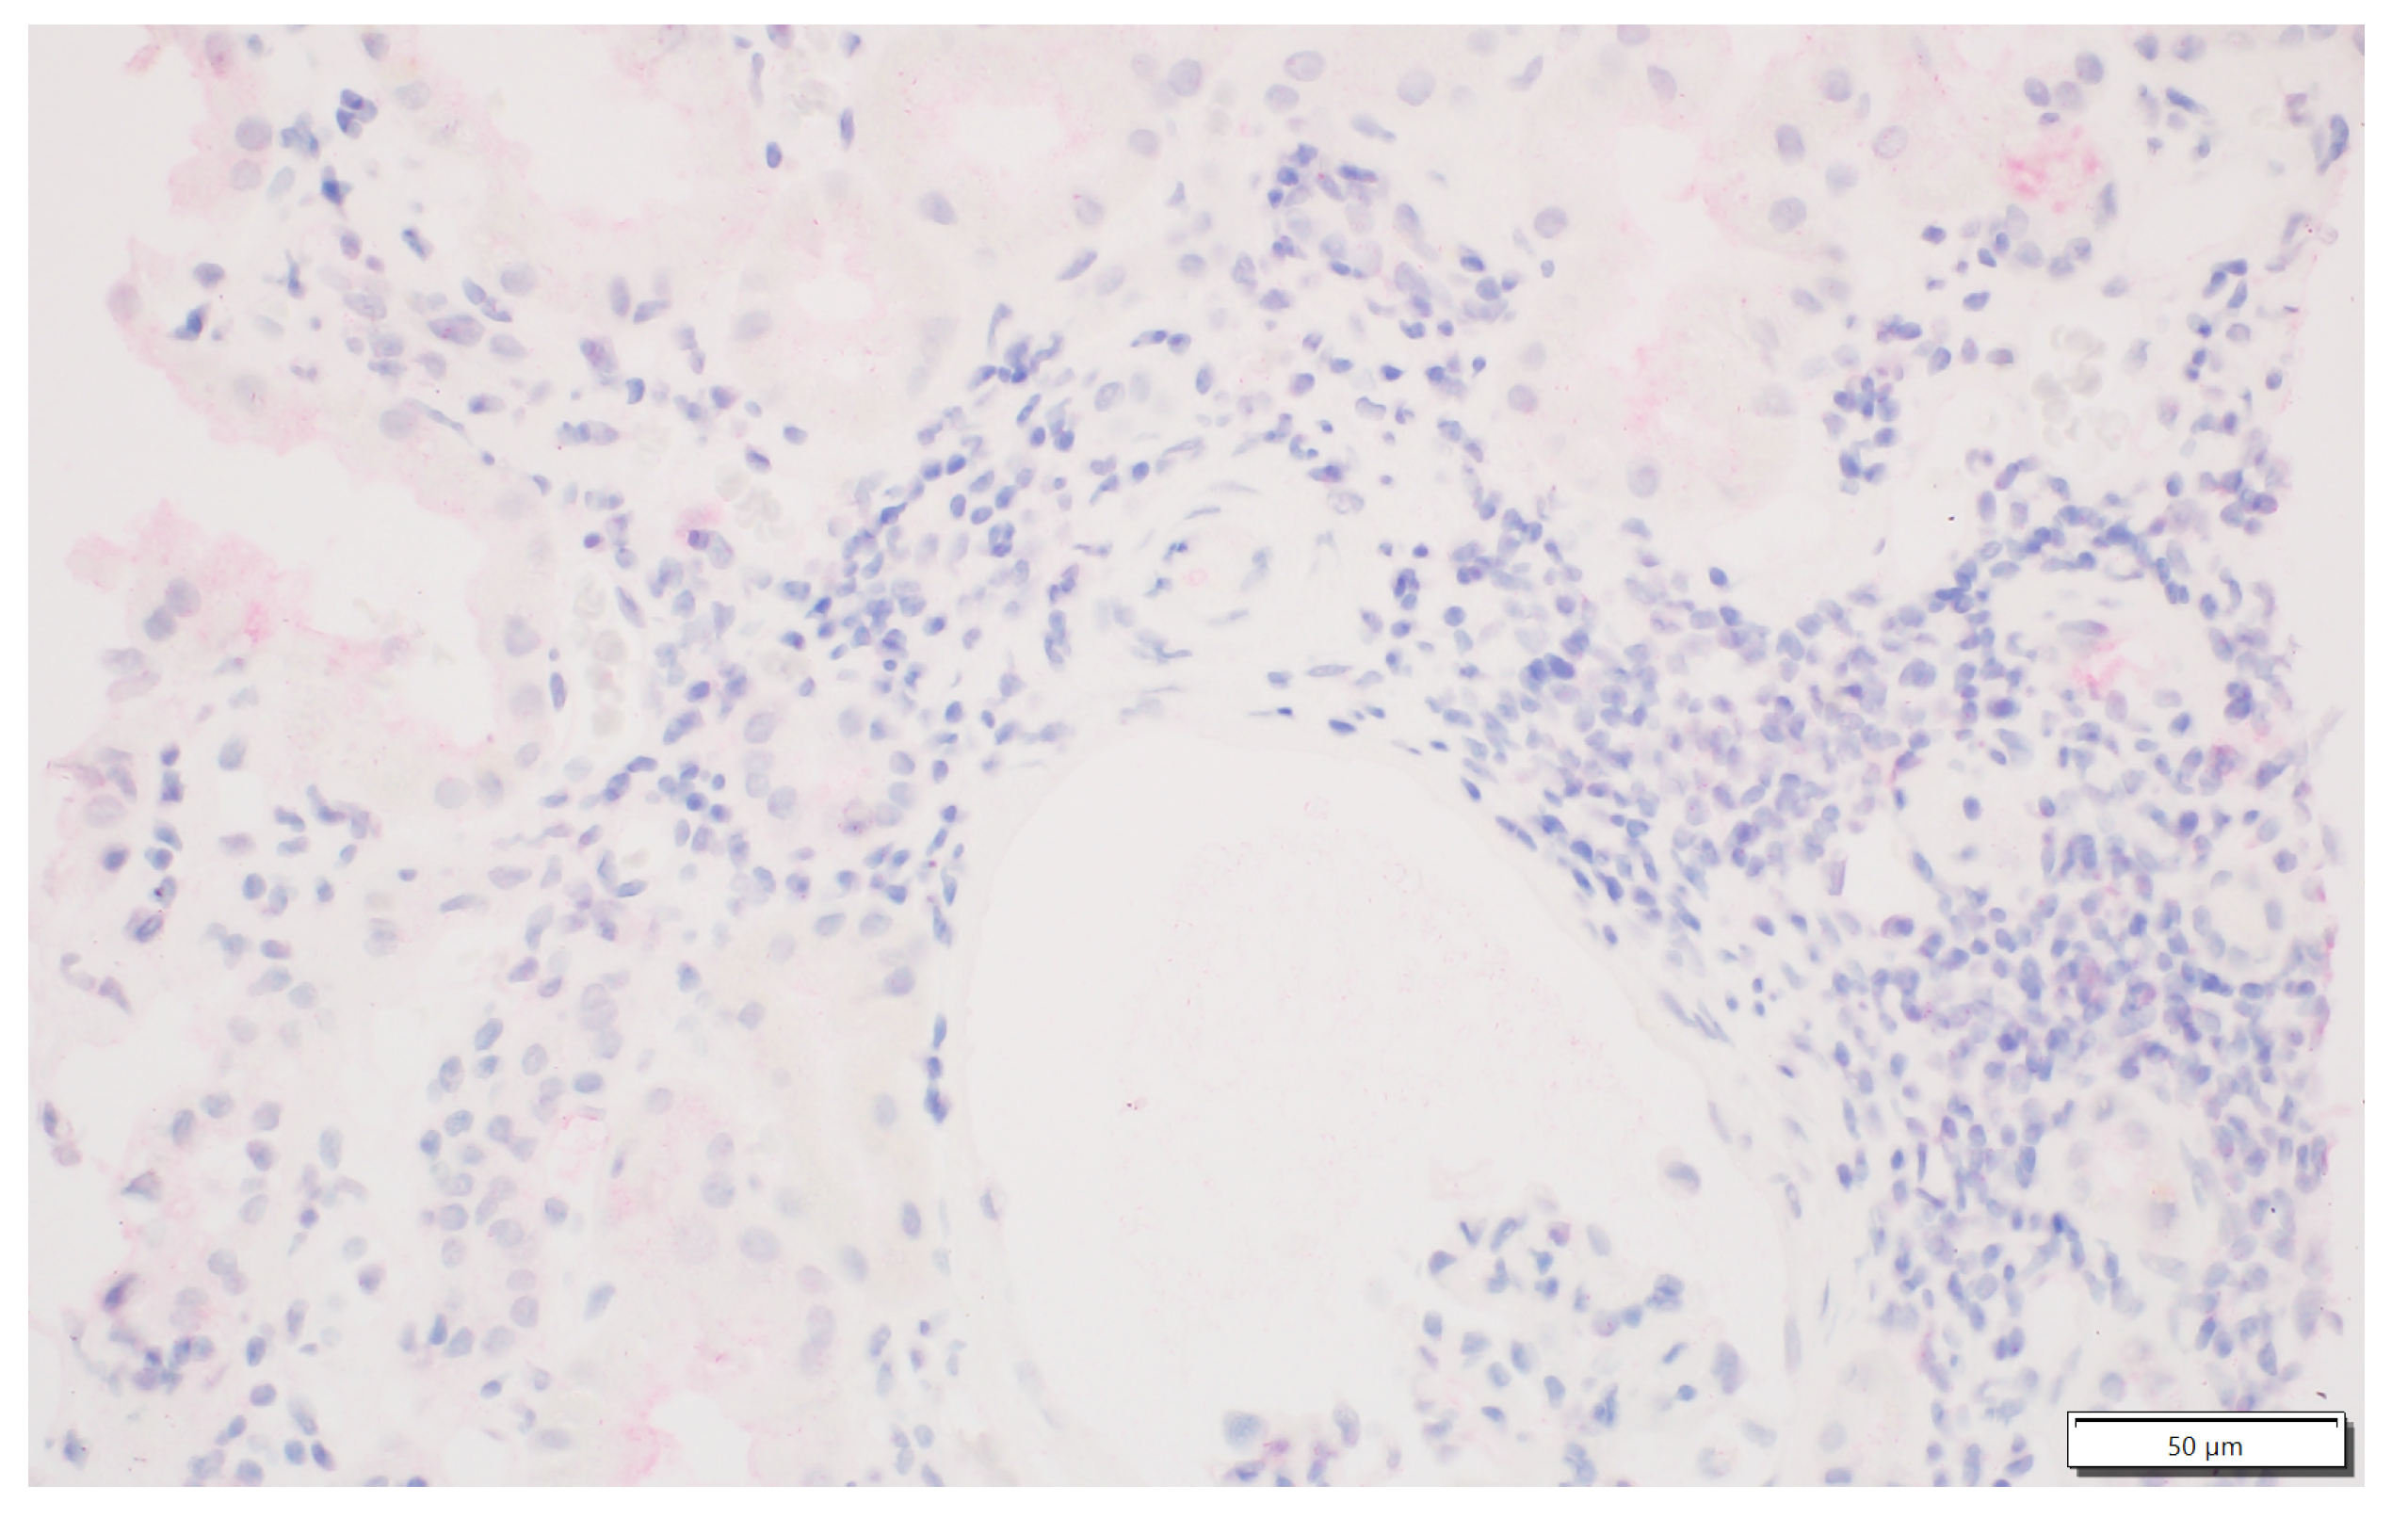

Figure 3.

Focal presence of IDO1-positive interstitial immune cells.

Figure 4.

Presence of IDO1 expression in the interstitial immune cells.

We analysed the expression of IDO1 in interstitial foci. The scoring system for IDO1 expression in interstitial foci was maintained on a binary scale, with ‘0’ indicating no IDO1 presence and ‘1’ indicating any presence of IDO1. This binary approach was adopted to assess the potential association of IDO1 presence in interstitial foci with graft rejection. Immunohistochemistry analyses were performed on tissue sections using primary 1F8.2 antibodies against IDO1 (Sigma-Aldrich, Burlington, MA, USA) [18]. The epitope retrieval and staining procedures, including EnVision Target Retrieval Solution (Agilent Technologies, Inc., Santa Clara, CA, USA) and the Autostainer Link 48 (Agilent Technologies, Inc., Santa Clara, CA, USA), were consistent with the earlier study [19,20,21]. It also applies to the detection system, Liquid Permanent Red (Agilent Technologies, Inc., Santa Clara, CA, USA) [22]. The system divided the division into two groups for research: the IDO1-IF(+) positive and the IDO1-IF(−) negative groups. This facilitated a comparative analysis between these groups regarding rejection in transplanted kidneys, causes of chronic renal failure, post-transplantation treatment and a comparison of patient characteristics within each group. The distinction between interstitial immune cells and tubular epithelium, which we focused on in our previous study, was based on detailed histopathologic analyses performed by experienced renal pathologists (PD and AH) [21]. Tubules are structures with lumen, and interstitial immune cells are dispersed and do not form tubular structures. To better showcase the process, Figure 1 shows no IDO1 expression in interstitial foci, and Figure 2 displays IDO1 activity in tubular epithelium in comparison, while Figure 3 and Figure 4 show IDO1 immunoreactivity in interstitial foci.